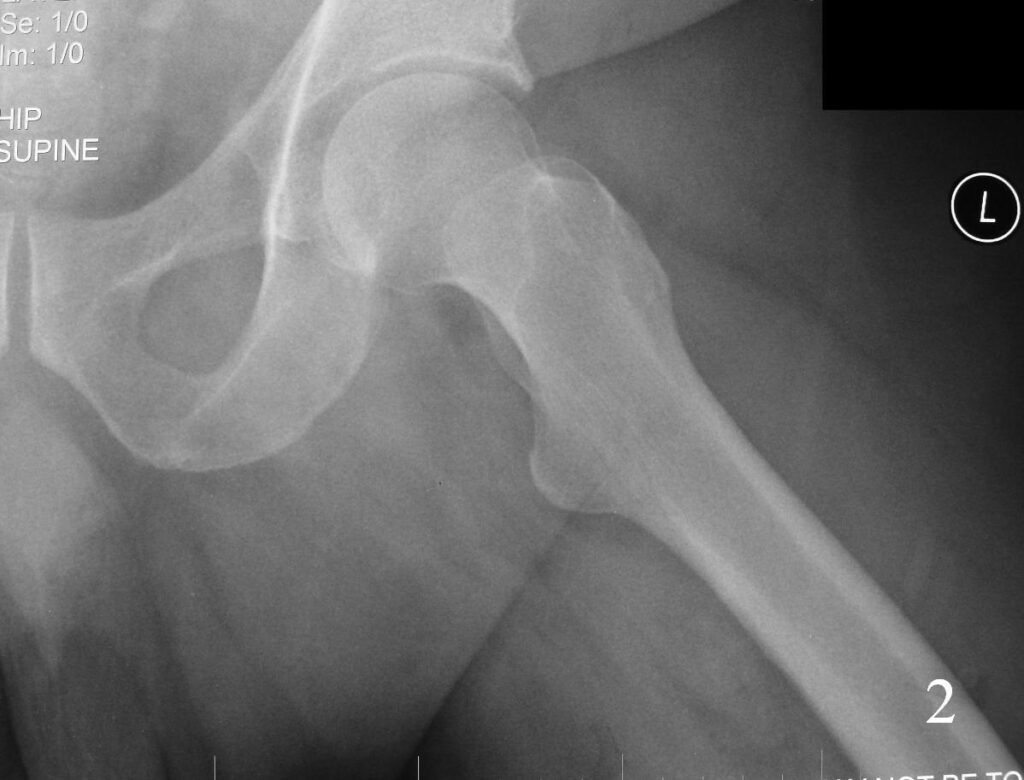

X-ray (Fig. 1-2)

Fig. 2

Fig 1-2. AP X-ray and lat (Fig. 2) of left hip shows a nonspecific soft tissue mass.